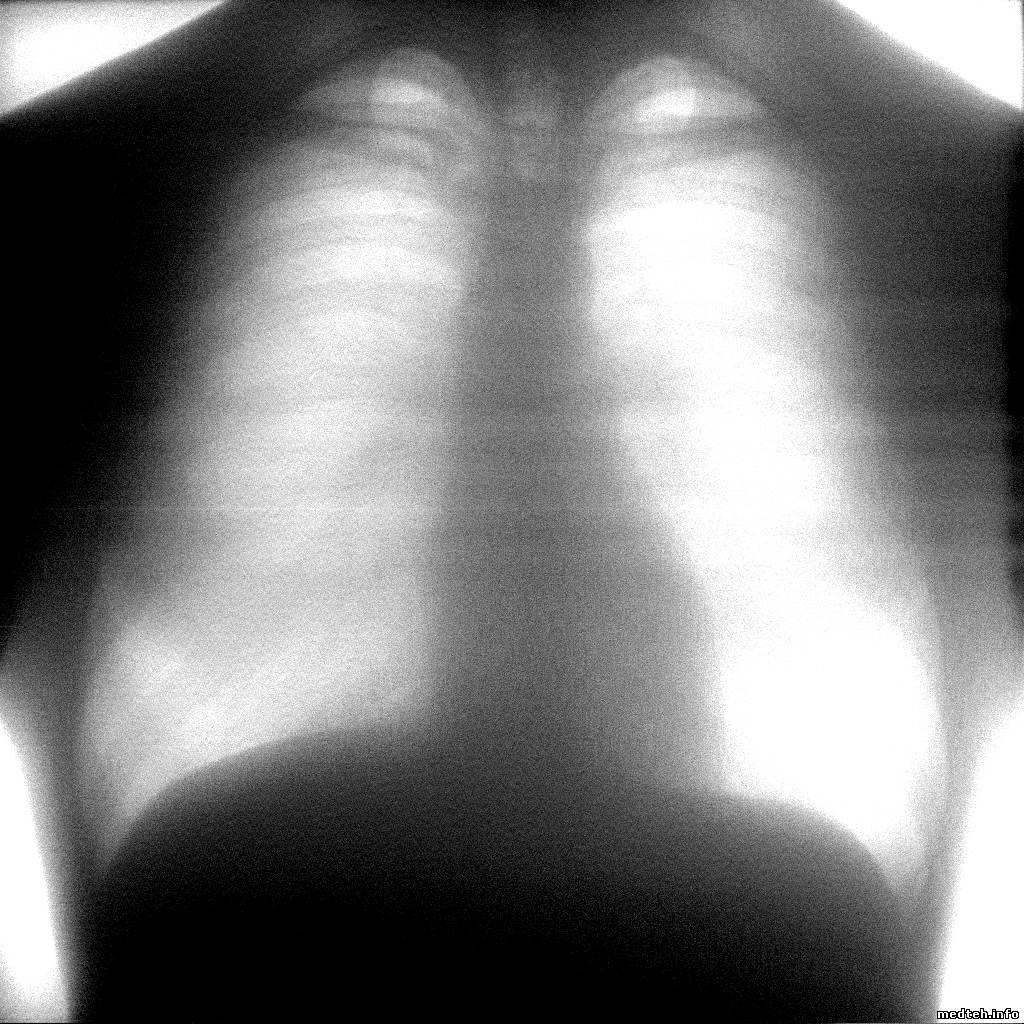

Образцы снимков:

7692566.jpg (773.1 Kb)